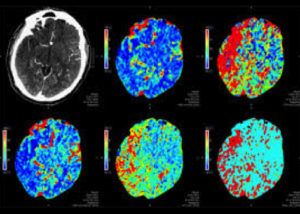

Many patients are treated with thrombectomy beyond the typical 6-hour time window. These patients are selected for treatment outside of the typical 6-hour window based on complex methods which typically include perfusion imaging (see color maps below). At ISC this year, we saw in the Trevo worldwide registry that fully 1/3 of thrombectomy patients received treatment in the > 6 hr time window and 1/5 of the thrombectomy patients in the Providence GWTG database were treated at greater than 6 hours. Patients treated in this delayed time window had worse discharge ranking scores but had no worse NIH stroke scale, length of stay. These data suggest that properly selected patients in the delayed time window derive almost as much benefit as patients treated in the early time window. Our research was presented as one of two studies detailing stroke transfer times and outcomes in data from 562 acute ischemic stroke patients with large vessel occlusions and is described in Clinical Neurology News.

Perfusion Imaging and Thrombectomy

In a pooled analysis of six thrombectomy trials, Dr. Bruce Campbell’s group showed that perfusion imaging combined with RAPID software strongly predicted outcome after thrombectomy. Specifically, patients who had thrombectomy had worse outcomes if they showed larger area of core infarct on perfusion imaging prior to their treatment. However, even for large volume infarcts at the time of thrombectomy, there was significant benefit to receiving the thrombectomy.